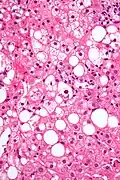

Mallory bodies are highly eosinophilic and thus appear pink on H&E stain. The bodies themselves are made up of intermediate cytokeratin 8/18 filament proteins that have been ubiquitinated, or bound by other proteins such as heat shock proteins, or p62/Sequestosome 1.[5]

Liver micrograph showing abundant Mallory bodies, as seen in alcohol use disorder. -